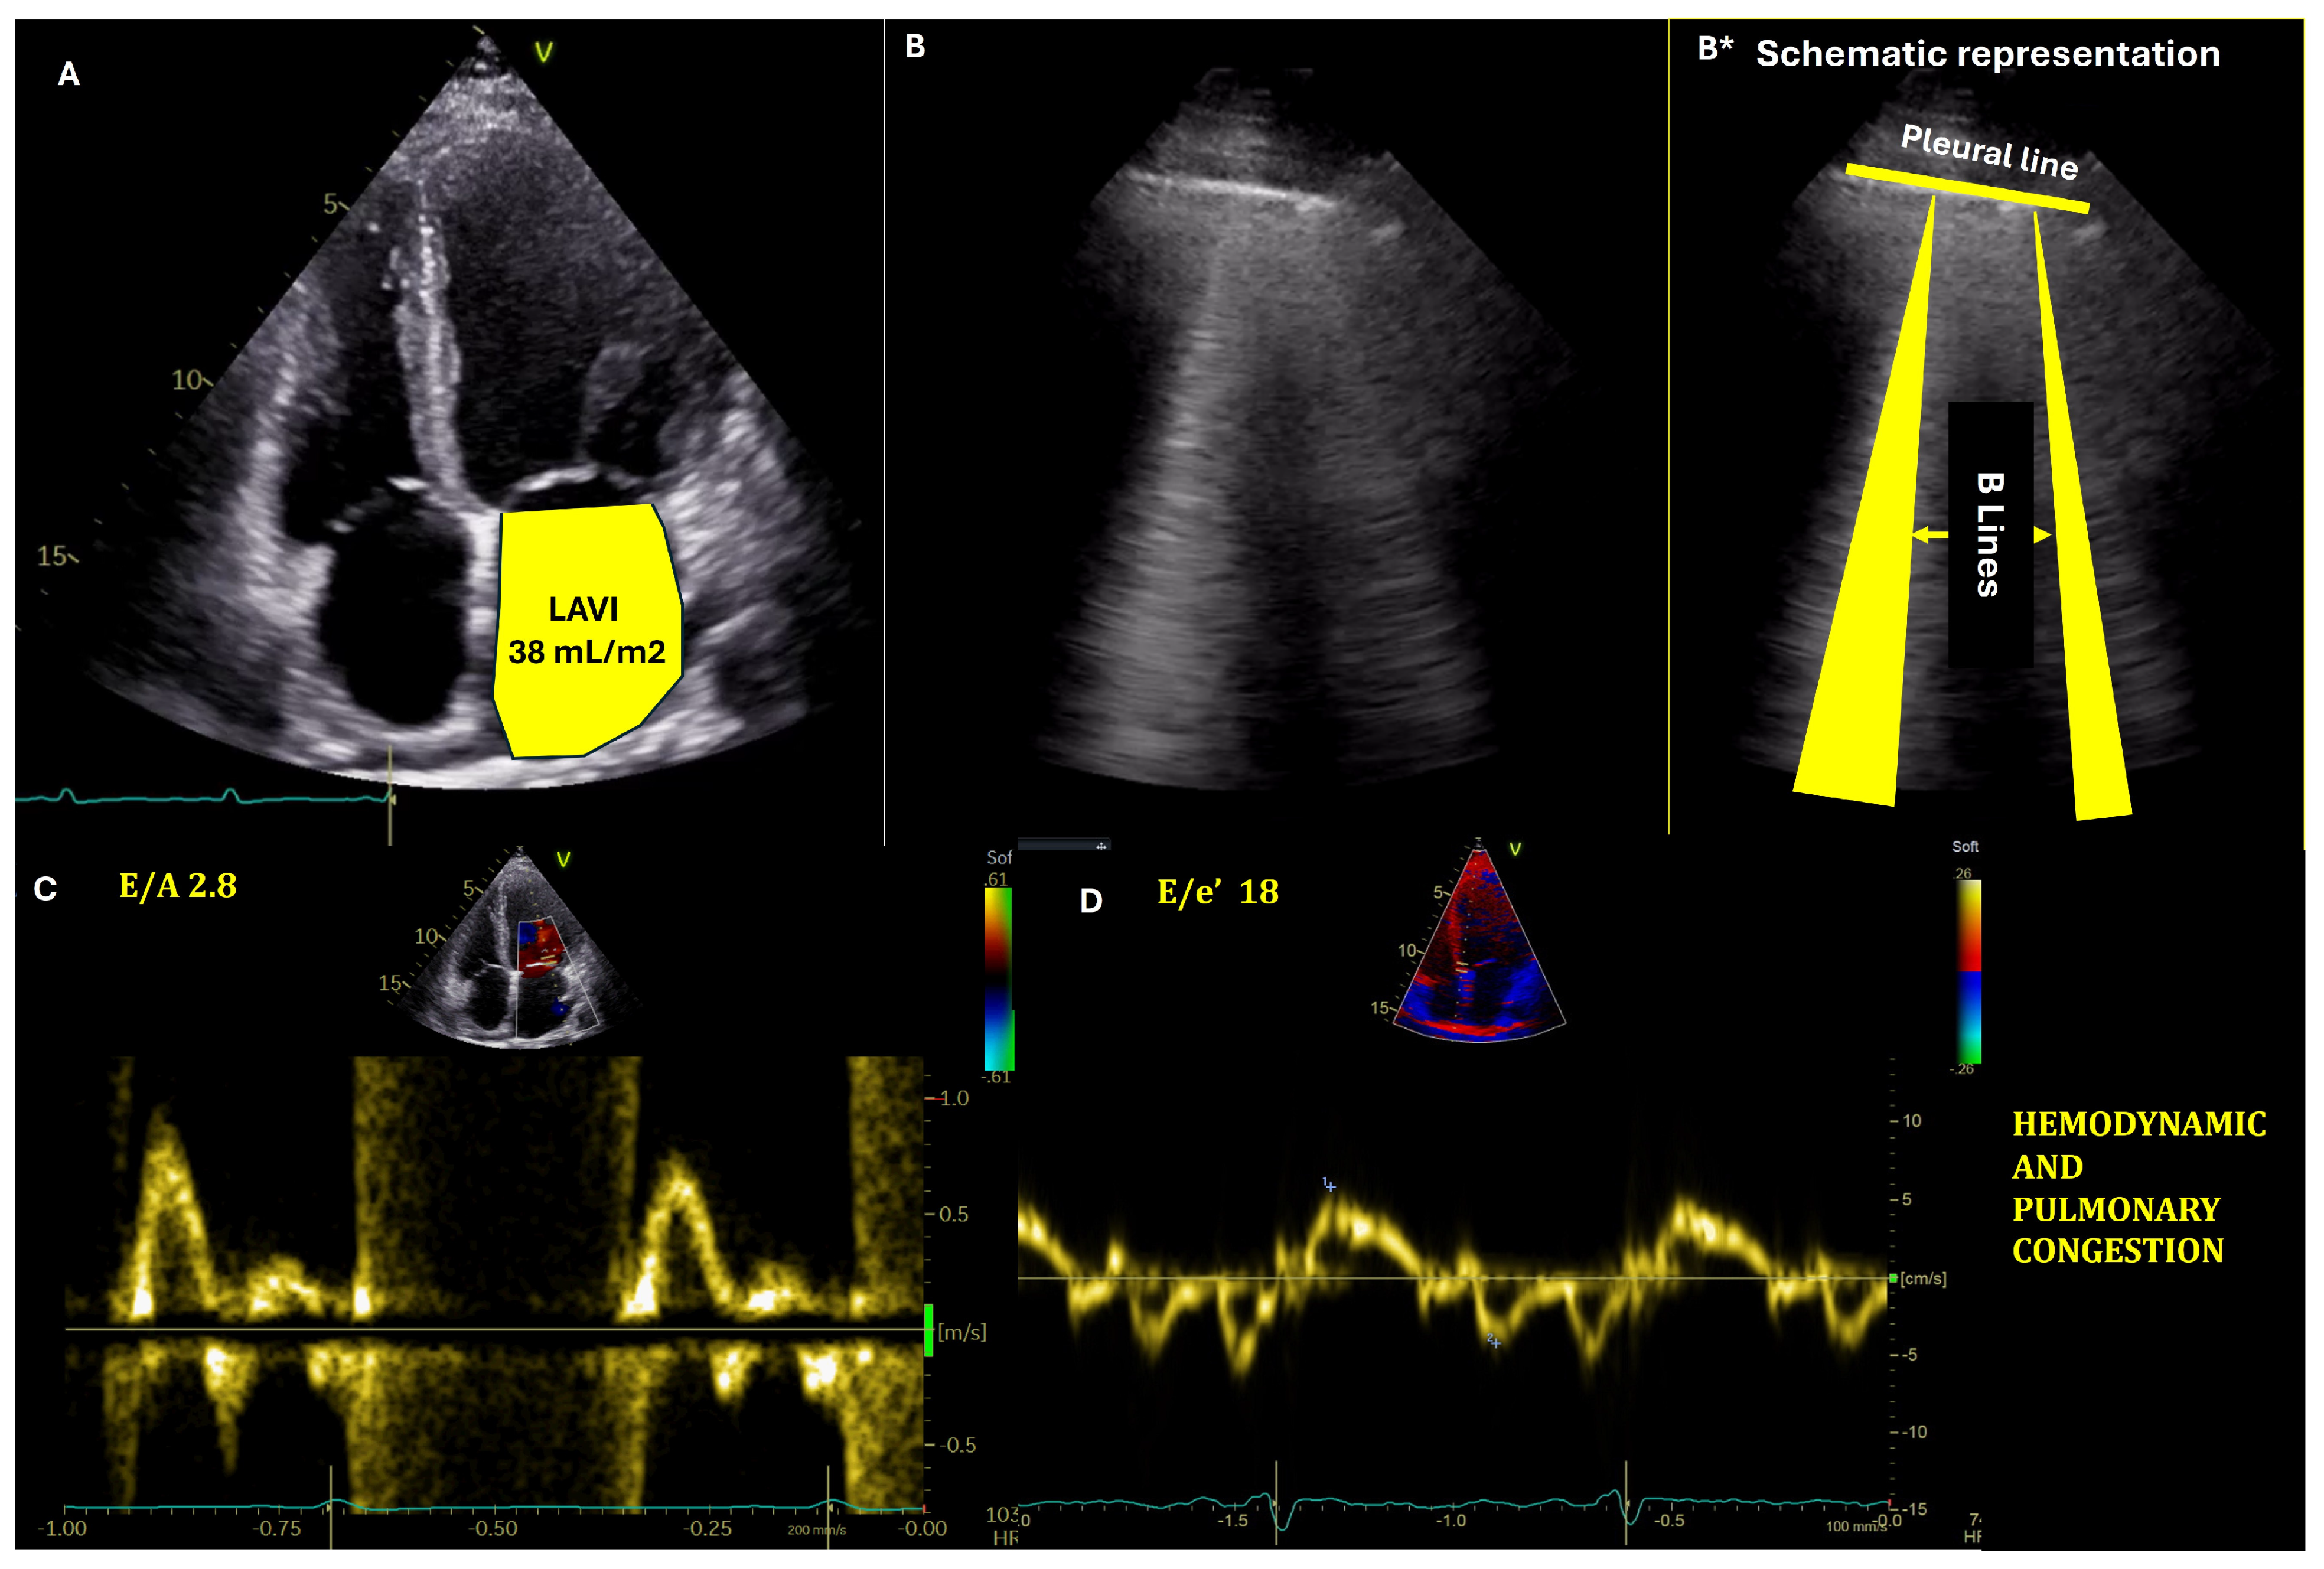

- Estimation of left ventricular (LV) filling pressures

| Echocardiography | Estimates LV filling pressures and assesses cardiac function. | Essential for managing HF; provides prognostic information. | Highly sensitive for assessing LVFP; useful in guiding therapy. | Predicts outcomes based on LVFP and cardiac function. |

- Andersen, O.S.; Smiseth, O.A.; Dokainish, H.; Abudiab, M.M.; Schutt, R.C.; Kumar, A.; Sato, K.; Harb, S.; Gude, E.; Remme, E.W.; et al. Estimating Left Ventricular Filling Pressure by Echocardiography. J. Am. Coll. Cardiol. 2017, 69, 1937–1948. [Google Scholar] [CrossRef] [PubMed]

- Shin, S.H.; Claggett, B.; Inciardi, R.M.; Santos, A.B.S.; Shah, S.J.; Zile, M.R.; Pfeffer, M.A.; Shah, A.M.; Solomon, S.D. Prognostic Value of Minimal Left Atrial Volume in Heart Failure With Preserved Ejection Fraction. J. Am. Heart Assoc. 2021, 10, e019545. [Google Scholar] [CrossRef]

- Hoit, B.D. Left atrial size and function: Role in prognosis. J. Am. Coll. Cardiol. 2014, 63, 493–505. [Google Scholar] [CrossRef]

- Smiseth, O.A.; Morris, D.A.; Cardim, N.; Cikes, M.; Delgado, V.; Donal, E.; Flachskampf, F.A.; Galderisi, M.; Gerber, B.L.; Gimelli, A.; et al. Multimodality imaging in patients with heart failure and preserved ejection fraction: An expert consensus document of the European Association of Cardiovascular Imaging. Eur. Heart J.-Cardiovasc. Imaging 2022, 23, e34–e61. [Google Scholar] [CrossRef] [PubMed]

- Lancellotti, P.; Galderisi, M.; Edvardsen, T.; Donal, E.; Goliasch, G.; Cardim, N.; Magne, J.; Laginha, S.; Hagendorff, A.; Haland, T.F.; et al. Echo-Doppler estimation of left ventricular filling pressure: Results of the multicentre EACVI Euro-Filling study. Eur. Heart J. Cardiovasc. Imaging 2017, 18, 961–968. [Google Scholar] [CrossRef]

- Cameli, M.; Lisi, M.; Mondillo, S.; Padeletti, M.; Ballo, P.; Tsioulpas, C.; Bernazzali, S.; Maccherini, M.; Colella, A.; Pierli, C.; et al. Left atrial longitudinal strain by speckle tracking echocardiography correlates well with left ventricular filling pressures in patients with heart failure. Cardiovasc. Ultrasound 2010, 8, 14. [Google Scholar] [CrossRef] [PubMed]